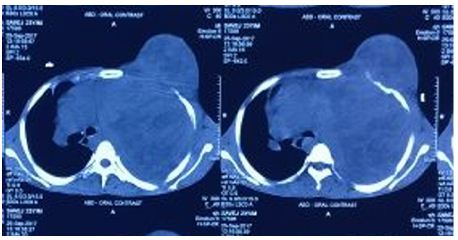

On ‘hook test’ (Figure 2) we could not hook finger around any anterior structures with elbow in flexed and supinated position. Pre operative quick DASH score was 57. X-ray showed no bony abnormality and an MRI confirmed complete rupture (Figure 3) and marked retraction of distal biceps tendon from bicipital tuberosity of the radius. Since the duration of injury was just one month we planned for reinsertion of tendon to bicipital tuberosity using fibre wire and an anchor screw. After pre anaesthesia evaluation patient was taken up for surgery. We went through anterior approach using a curved single incision over antecubital fossa without a tourniquet, and retrieved the tendon from the superior part of the incision (Figure 4).

Figure 3: MRI showing complete rupture and marked retraction of distal beceps tendon from bicipital tuberosity of radius.